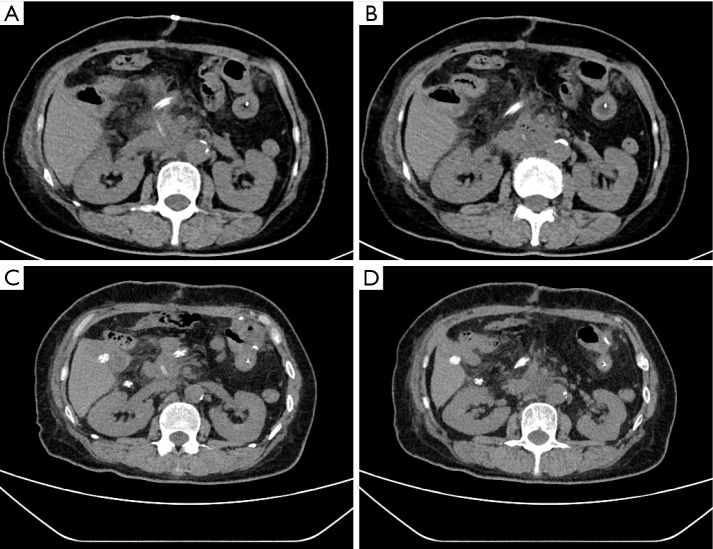

Case description: This report describes a 59-year-old female patient who underwent radical pancreaticoduodenectomy for pancreatic ductal adenocarcinoma (T2N0M0). On the 8th postoperative day, she developed back pain, followed by a sudden increase in body temperature, elevated inflammatory markers, and a significant increase in amylase levels in the drainage fluid. Enhanced abdominal computed tomography revealed that one side of the pancreatic duct support tube had penetrated the abdominal cavity, resulting in posterior peritoneal effusion. Emergency removal of the support tube and repair of the intestinal perforation were performed. The patient had an uneventful recovery after surgery and was discharged on day 20 following the second operation.